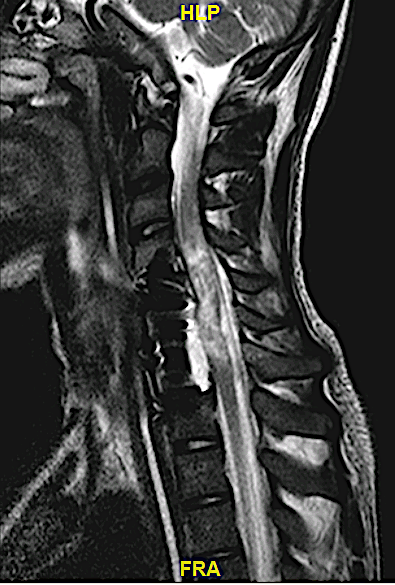

RM cervical postoperatoria

Se realizó un abordaje anterior, con corpectomía C6 y C7 y discectomía C4-C5. Arriba se colocó una caja atornillada mientras que las dos vertebrectomías fueron rellenadas con una prótesis vertebral expansible de titanio + placa cervical + hueso autólogo. El paciente presentó una fístula de LCR (al estar la duramadre lacerada por la fractura) que no precisó revisión quirúrgica.

Obsérvese (no hay RX cervical de control) la recuperación del perfil cervical fisiológico obtenido tras la reconstrucción así como el daño medular extenso que presenta.

En mi opinión, las prótesis vertebrales expansibles facilitan mucho la cirugía y quedan perfectamente ajustadas a los platillos (deben estar intactos). Respecto a la escasez de injerto que se supone al variar su longitud, considero que éste puede ser restituido por los laterales y cara anterior previo a la colocación de la placa cervical.